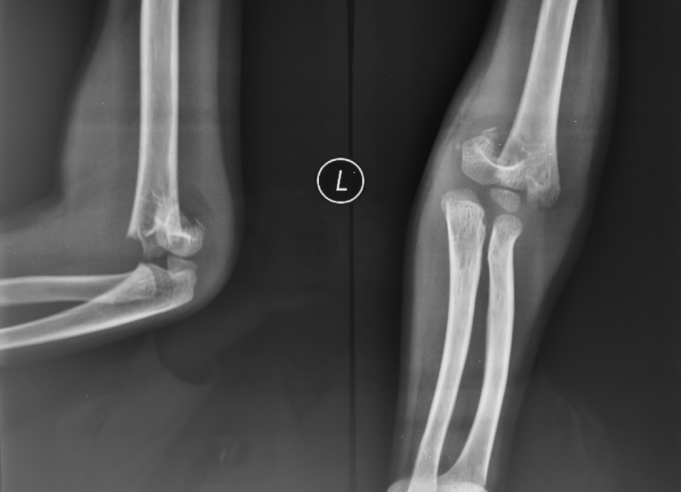

2、小雨(化名):女、8岁、在小区游乐场吊单杠时不慎摔伤致右肘部肿痛、畸形、活动受限1小时就诊我院。(下图为患儿术前X线片)